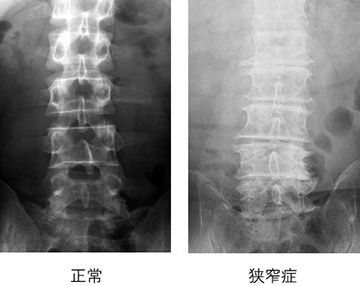

①レントゲン検査

骨の変形や椎間板の傷みの程度がわかります。狭窄症では椎間板がつぶれて、骨が変形しています。